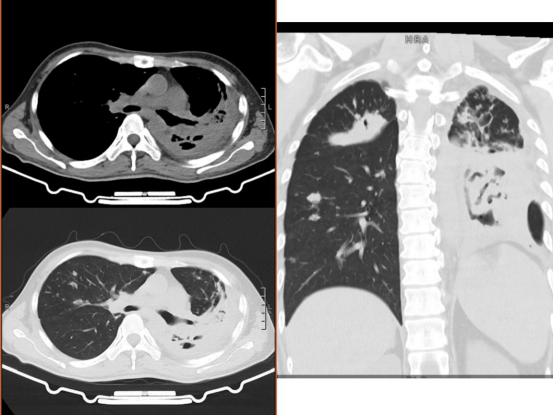

患者經(jīng)手術(shù)治療后轉(zhuǎn)入重癥醫(yī)學(xué)科時情況

術(shù)后患者仍面臨著余肺氧飽和度不能維持、肺部結(jié)核感染、膿毒血癥等眾多威脅患者生命安全的因素,在ICU主任陳佳的帶領(lǐng)之下,ICU醫(yī)護團隊用專業(yè)和熱忱幫助患者逐步控制感染和結(jié)核情況。患者逐漸從術(shù)后僅能靠呼吸機維持氧飽和度,到氣管切開后脫離呼吸機;10月23日,患者拔除氣管切開套管,已能完全經(jīng)口鼻自主呼吸;10月29日,患者已康復(fù)出院。